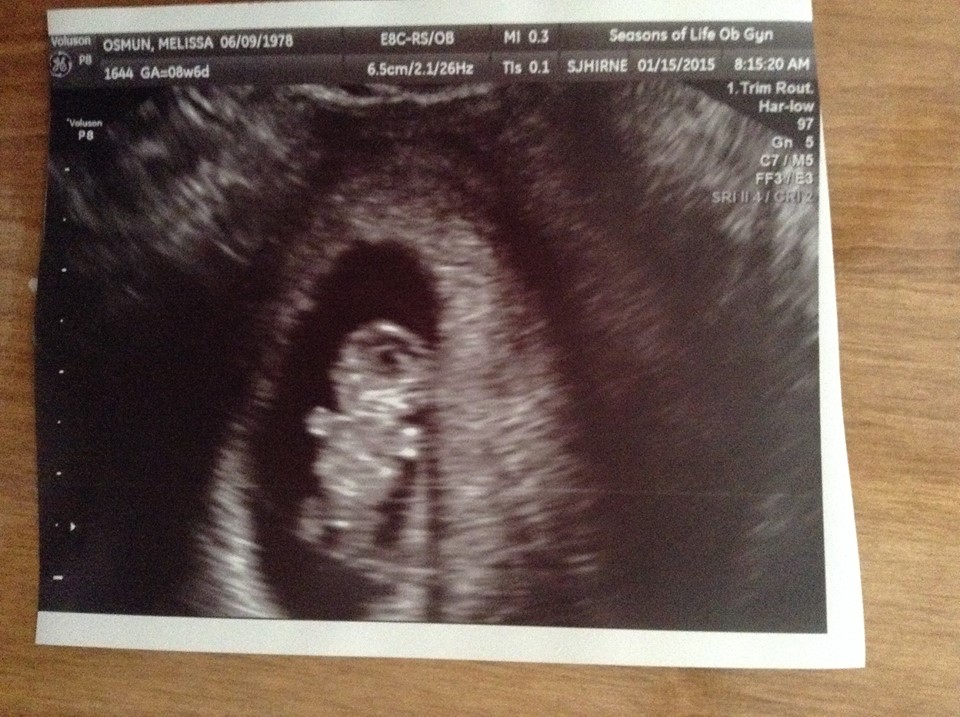

I feel like I can finally be excited about being pregnant.  We saw a little gummy bear today with a strong heartbeat of 178.  I measured 9w or 9w 1d, depending on what was being measured.  I have been going by 8w 3d based on ovulation.  The doctor is going to stick to my LMP and say I am 8w 6d.  So I will be moving to the Friday Ticker Change posts.